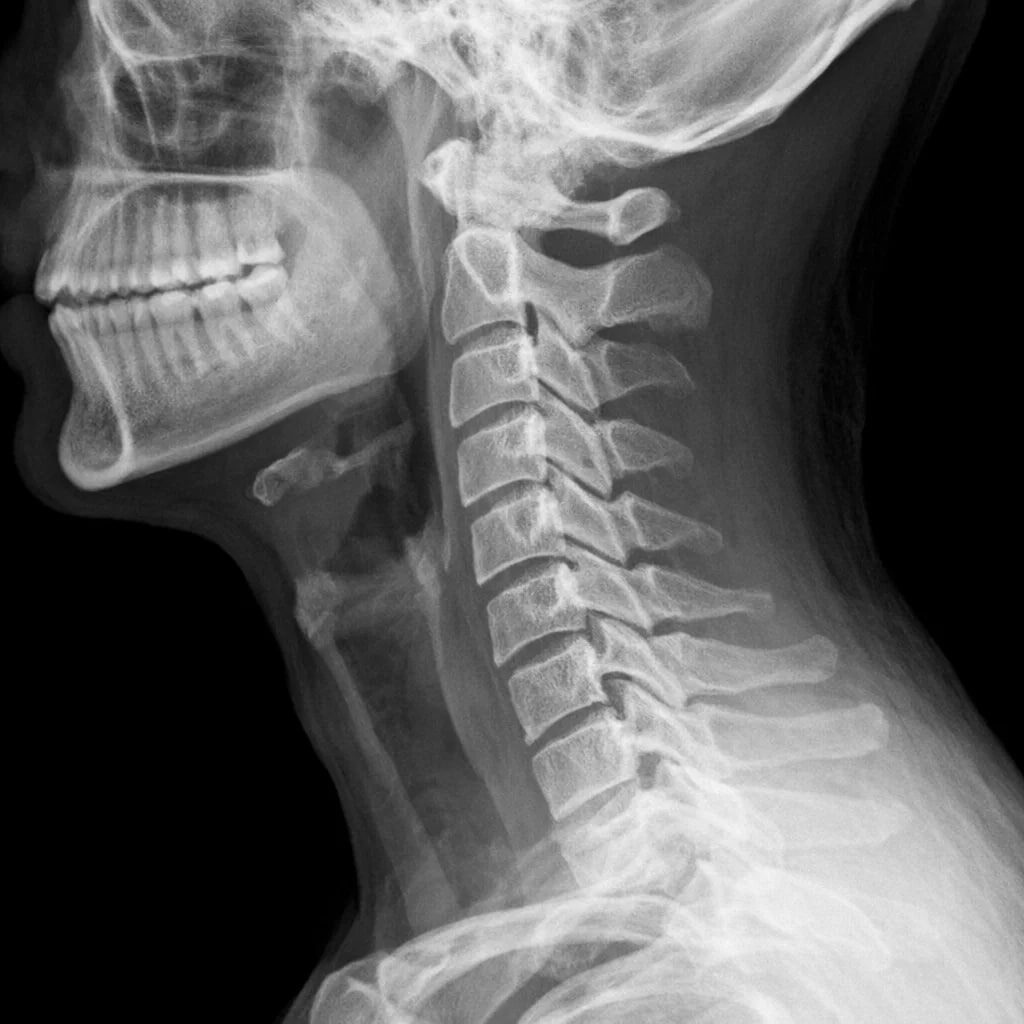

Боль в пальцах часто автоматически считают артритом Но суставы могут быть полностью здоровы ПОЧЕМУ ТАК БЫВАЕТ 🧠 Нервы, идущие к кистям Выходят из шейного и верхнегрудного отдела позвоночника Если там есть — спазм — перегрузка — протрузия — хроническое напряжение Сигнал искажается И боль ощущается в пальцах КАК ЭТО ПРОЯВЛЯЕТСЯ ⚠️ — жжение или ноющая боль — онемение — покалывание — скованность — анализы на артрит в норме ВАЖНЫЙ ПРИЗНАК ❗️ Если боль меняется от положения шеи Или усиливается при движении Проблема может быть не в пальцах А в позвоночнике